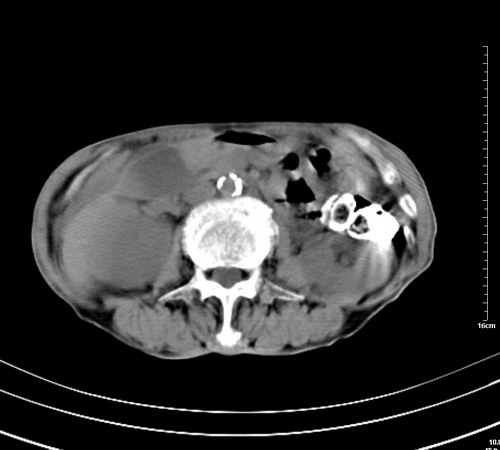

病人,女,79岁,主要因腹疼二月入院,彩超,肝,胆,脾,未见异常,胸透上消化道造影未见异常,化验白细胞增高,内科医生让做胸部ct检查,因为熟人多做了腹部(外科会诊考虑胆囊炎).现ct片如下请假各位战友.

1 气管旁、隆突下淋巴结明显肿大,肝左叶外侧段低密影,都考虑转移。

2 肝右后叶下段明显增大,片状低密影,但因各种伪影显示不佳,不排除病变。

肺癌,纵隔淋巴结转移,肝左叶病变考虑为转移病灶。

后中纵隔团块影,伴气管、食道受压移位,首先考虑转移瘤,肝s5段低密度灶。建议增强检查,另外其结肠是否有问题请提供,右肺部分肺叶局限含气增多,考虑局限肺气肿。

后中纵隔团块影,伴气管、食道受压移位,首先考虑转移瘤,肝表现同11773。